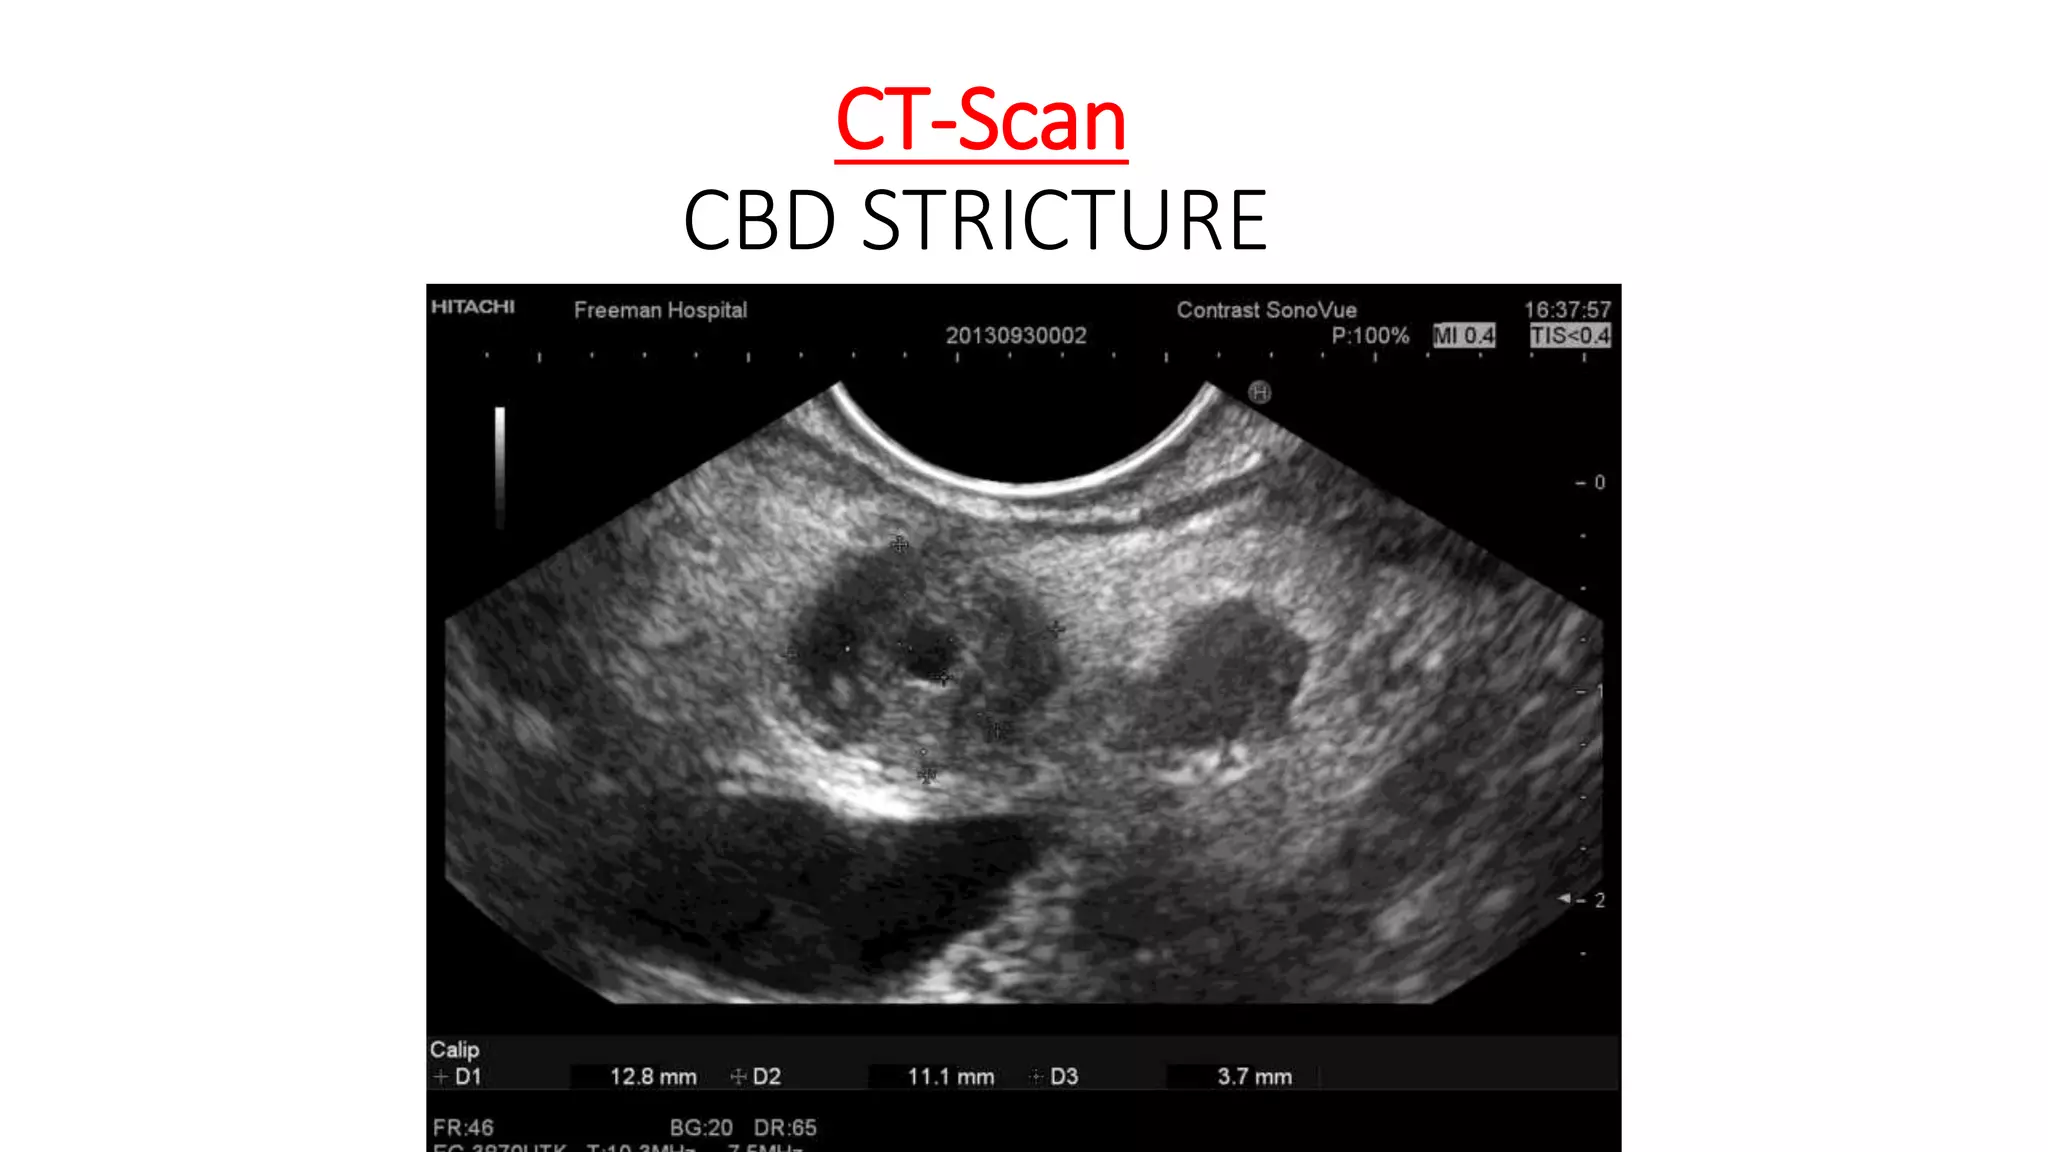

COMPUTED TOMOGRAPHY ( CT-Scan )

• It allows visualization of the liver, bile ducts, gall bladder and

pancreas.

• It is the modality of choice in the staging of cancers of the liver, gall

bladder, bile ducts and pancreas.

• Improvements in CT technology, such as multi-detector scanners,

which allow for three-dimensional reconstruction of the biliary tree

have led to greater diagnostic accuracy and have increased the

accuracy of CT in assessing benign disease.

CT-Scan

Gall Stone CBD Stone

CA HEAD OF PANCREAS

CBD STRICTURE